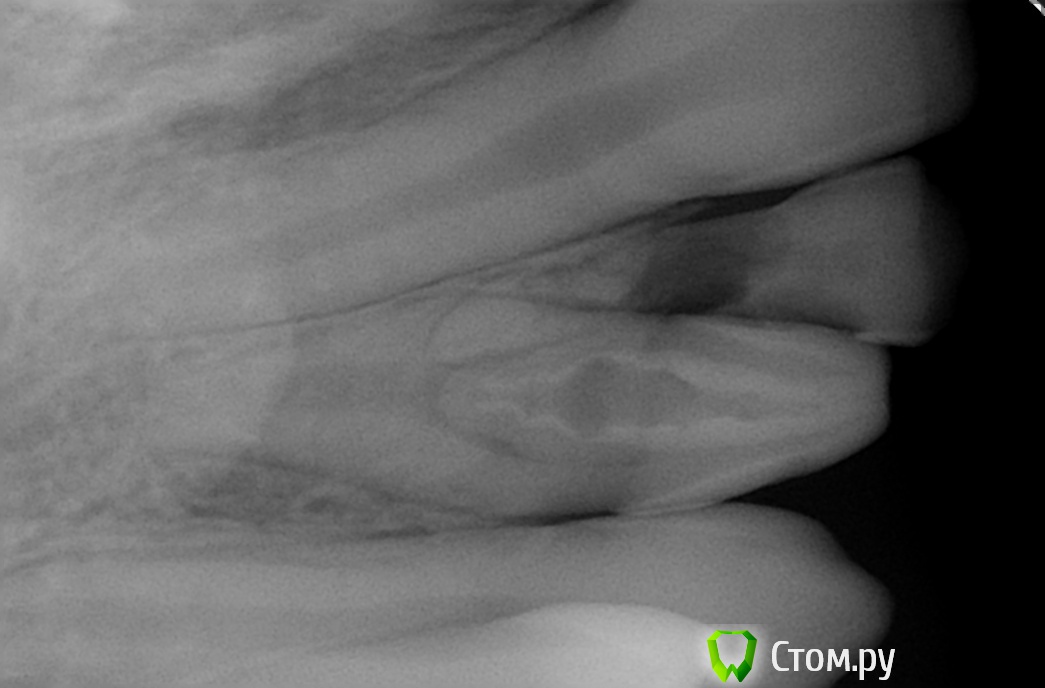

SergeiVar Опубликовано 10 июля, 2014 Поделиться Опубликовано 10 июля, 2014 Жалобы на наличие молочного зуба рядом с постоянным. На прицельном снимке в пльповой камере постоянного 12з. дентикль или зуб в зубе? Ссылка на комментарий

wladdX Опубликовано 10 июля, 2014 Поделиться Опубликовано 10 июля, 2014 (изменено) Похоже на инвагинат Изменено 10 июля, 2014 пользователем wladdX 4 1 Ссылка на комментарий

Джима Опубликовано 10 июля, 2014 Поделиться Опубликовано 10 июля, 2014 (изменено) он и есть.Я бы снимок сохранила для коллекции - прикольный. жалоб на него нет? зуб витальный? загерметизировать бы его, пока не поздно. Изменено 10 июля, 2014 пользователем Джима 1 Ссылка на комментарий

SergeiVar Опубликовано 11 июля, 2014 Автор Поделиться Опубликовано 11 июля, 2014 жалоб никаких, пришли молочную двойку удалять.завтра если в архиве найду еще один похожий снимок выложу.пс. какие жалобы могут быть? Ссылка на комментарий

Джима Опубликовано 12 июля, 2014 Поделиться Опубликовано 12 июля, 2014 пс. какие жалобы могут быть?ну, инвагинаты имеют свойство портиться внутри и внезапно давать периодонтит практически без видимых причин. 1 Ссылка на комментарий